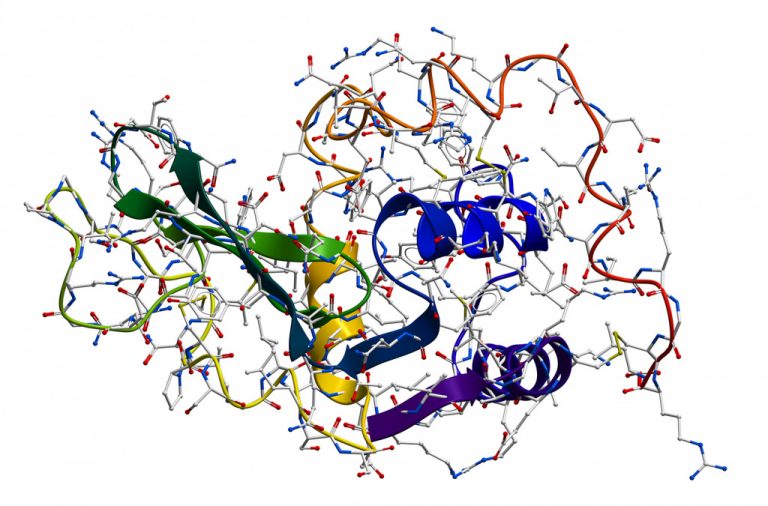

Коли шкідливі мікроби намагаються прорвати бар’єри слизових оболонок, на передовій стає лізоцим – скромний, але потужний фермент,...